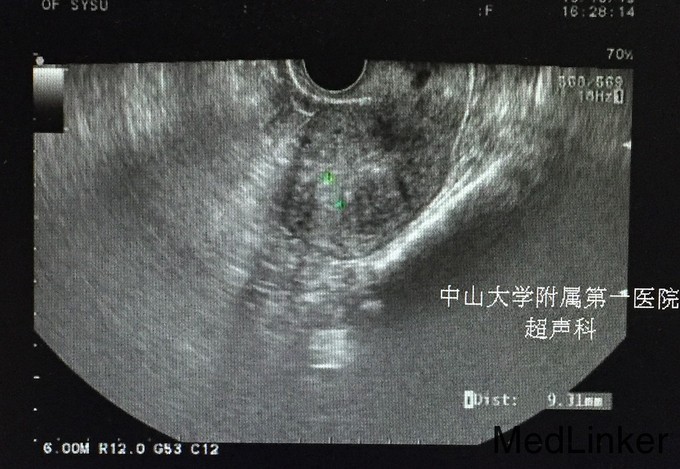

查体:;宫颈轻度糜烂,余未见异常。 辅查:.2015-10-04妇科B超:子宫增大,子宫肌瘤(后壁2.2cm*2.1cm),子宫内膜增厚,约1.8cm。 2015-10-10诊刮病理示:慢性子宫内膜炎,局部符合子宫内膜息肉,分泌期子宫内膜。 2015-10-25我院妇科B超:小型子宫肌瘤。(见图)

诊断:1.异常子宫出血:子宫内膜息肉(多发性)?2.月经过多 治疗:宫腔镜检查+子宫内膜射频消融术, 宫腔镜下见:宫颈管通畅,宫腔形态正常,双侧输卵管开口清晰,子宫内膜不厚,未见明显赘生物和突起,刮出内膜送病理。探子宫腔深9.0厘米,宫颈深度4.0cm。设置宫腔深5.0cm,宽4.6cm,功率121w,启动后射频工作时间69s。 再次宫腔镜下检查,见宫腔包括两侧宫角基本消融,呈焦黄色。宫颈管内膜未破坏。术毕。